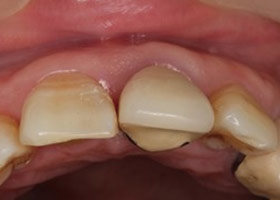

假牙拆除後,因續發性齲齒已深至牙肉下,且牙根明顯鬆動,遂無法保留牙根。

因美觀問題,採取拔牙後立即植牙。(此種治療方式須經醫師評估)

植牙後,立即利用舊牙套轉換成臨時性假牙。